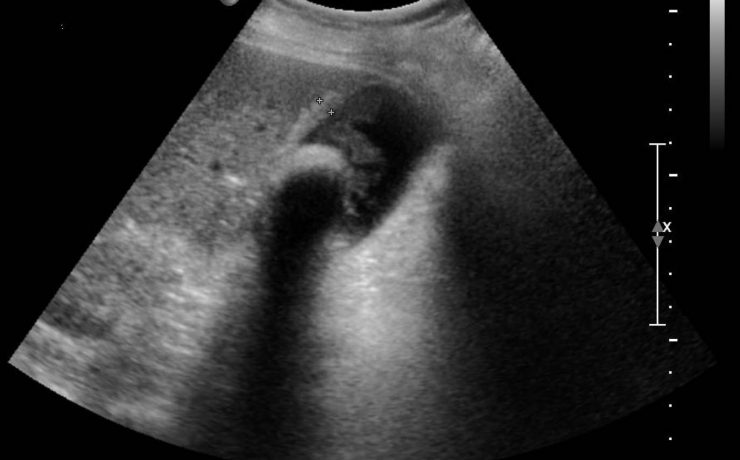

Evaluación del Puntaje Ultrasonográfico para el diagnóstico diferencial de lesiones sólidas de mama.

Este estudio fue realizado por el Hospital Universitario de Harbin, China y publicado en el 2009 por la Revista de la Sociedad Médica de Diagnóstico Sonográfico. El artículo propone un puntaje basado en 8 características ultrasonográficas de las lesiones sólidas de mama para diferenciar las